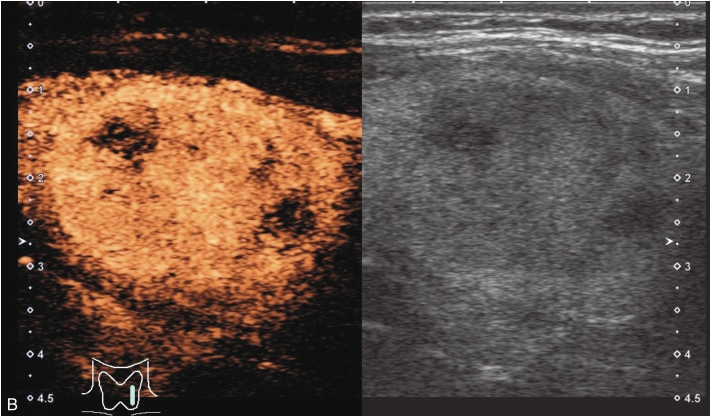

女性,56岁,体检超声发现甲状腺结节1周,无不适。甲状腺功能正常,实验室检查:FT3 3.76pmol/L,FT4 11.68pmol/L,TSH 2.8414μIU/ml。手术病理提示结节性甲状腺肿。

甲状腺形态基本正常,甲状腺实质回声稍增粗,分布尚均匀,甲状腺包膜尚光滑。甲状腺两叶内见多发结节,较大者位于左叶上极,呈类椭圆形,边界清楚,形态规则,纵横比<1,内部回声均匀,未见钙化,后方回声稍增强。CDFI显示左叶较大结节边缘可见丰富的条状血流信号,内部可见条状、点状血流信号,见图1-3-7。

图1-3-7 结节性甲状腺肿常规超声表现

A.常规超声图像;B.CDFI超声图像

甲状腺左叶上极较大结节增强早期呈稍高增强,自结节外周向中央灌注,增强晚期呈等增强,结节内部可见不均匀低增强区,见图1-3-8、ER1-3-4。

图1-3-8 结节性甲状腺肿超声造影图像

ER1-3-4 结节性甲状腺肿的超声造影

结节性甲状腺肿超声造影表现为病变多与周围正常甲状腺组织呈同步等或高增强,增强多较均匀,伴有囊性变者,内部可见无增强区,增强后结节边界清,周边可见环状增强,增强晚期呈等或稍高增强,也可呈稍低增强。

多早于周围正常甲状腺组织增强,从周边向中心快速充盈,呈均匀性高增强,增强后结节边界清,形态较规则,周边亦可见环状增强。

造影后结节大多呈同进或慢进,以不均匀性低增强多见,也可呈等或高增强,增强后结节边界不清,形态不规则,增强晚期可呈低增强或等增强。

图1-3-10 结节性甲状腺肿超声造影图

A.增强早期结节呈同步不均匀性等增强;B.增强晚期呈不均匀性低增强